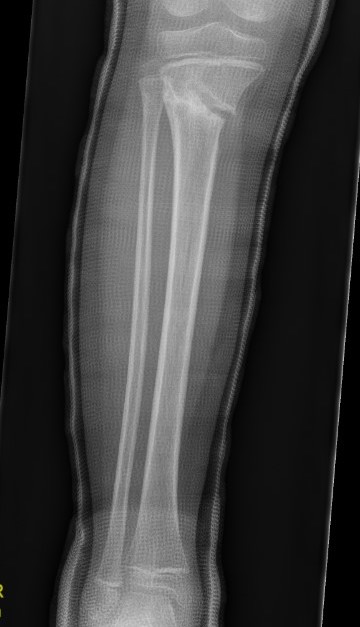

Correct valgus malalignment

- manipulate under anesthesia

- extension long leg cast with varus mould

Manipulation and casting of malaligned Cozen fracture under anesthesia